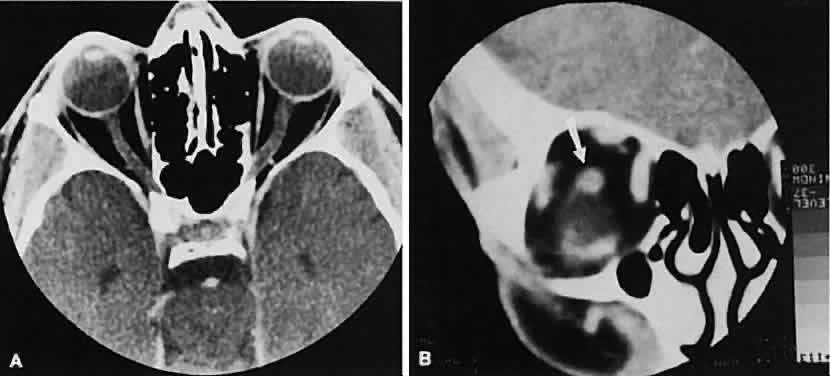

and colleagues49 suggested a differential approach based on high-resolution CT morphology. An enlarged optic nerve also is associated with an age-related differential diagnosis. Most gliomas are found in children, whereas optic nerve sheath meningiomas tend to afflict adults, primarily women. Nevertheless, there are exceptions for each. Optic nerve gliomas are associated with neurofibromatosis. A prospective study determined that a child with known neurofibromatosis has a 15% chance of having a glioma of the anterior visual pathway. Conversely, a child with an optic nerve glioma has a 25% chance of having neurofibromatosis.50 Although an optic nerve meningioma can occur in association with neurofibromatosis, particu-larly NF-2,51 the association is not as firmly established as with gliomas. It is uncommon but well-established that optic nerve meningiomas can occur during childhood. Not only can they create confusion regarding differentiation from optic nerve glioma, but, most important, they behave in a more aggressive fashion.52 The CT evaluation of optic nerve lesions is facilitated by the use of 1.5-mm axial slices and intravenous contrast.49 Gliomas usually appear as a fusiform enlargement with sharp delineation from the surrounding tissue due to circumscription by an intact dura (Fig. 10). Kinking and buckling of the optic nerve along with infarctive cysts are typical findings in an optic nerve glioma. Bilaterality and intracranial involvement of the anterior visual pathway also may be noted. The radiographic signature of an optic nerve meningioma is more variable (Fig. 11). The optic nerve shadow tends to be diffusely enlarged, with irregular expansion along the optic nerve. Jakobiec and colleagues53 found diffuse enlargement of the optic nerve with apical expansion to be the most frequent pattern. Calcification within the optic nerve shadow, which is unusual in optic nerve gliomas, is common with optic nerve meningioma. The irregular excrescent margins most likely signify extradural invasion into the adjacent orbital soft tissues. A central linear lucency extending the length of the optic nerve shadow also is a typical finding of an optic nerve meningioma.49 These two lesions represent the most frequent tumors affecting the optic nerve. Other reported tumors include hemangioblastoma, leukemic infiltration, and involvement by metastatic disease. Enlargement of the dural sheath around the optic nerve, an optic nerve meningocele, can be confused with a tumor.54 The radiographic procedure of choice for evaluating suspected optic nerve lesions is MRI with gadolinium and high-resolution, fat-suppression techniques. ORBITAL TUMORS In a patient with an orbital mass, CT can show not only the mass but also other valuable information such as shape, location, consistency, intralesional calcium, and effect on surrounding structures.55 Contrast enhancement offers some ideas about vascularity. VASCULAR TUMORS The vascular tumors under consideration are capillary hemangioma, cavernous hemangioma, lymphangioma, and hemangiopericytoma. Capillary hem-angiomas and lymphangiomas are benign infiltrativetumors seen in a pediatric population. Capillary hemangiomas have a homogeneous consistency, display intense uniform contrast enhancement, and do not usually displace any orbital structures (Fig. 12). Phleboliths are a characteristic finding in hemangiomas and, when present, are virtually pathognomonic of this diagnosis.56 Lymphangiomas have a cystic component, which, on occasion, may hemorrhage into itself, accounting for rapid onset of symptoms and clinical/radiographic evidence of mass effect (Fig. 13). In all likelihood, scans require sedation for an adequate study. Thin (1.5-mm) axial views with computer reformatting for coronal views along with contrast enhancement should provide an adequate study.

Both cavernous hemangiomas (Fig. 14) and hemangiopericytomas typically are seen in adults. Their radiographic appearance is similar and shows a well-demarcated, contrast-enhancing mass, although more intense enhancement may be seen with the hemangiopericytoma. The differential diagnosis of a well-demarcated, contrast-enhancing lesion is listed in Table 3.